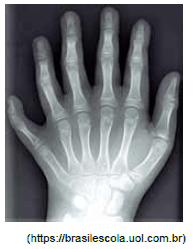

A figura apresenta a radiografia da mão de uma menina portadora de polidactilia, uma anomalia genética que consiste na alteração quantitativa anormal dos dedos das mãos (quirodáctilos) ou dos pés (pododáctilos).